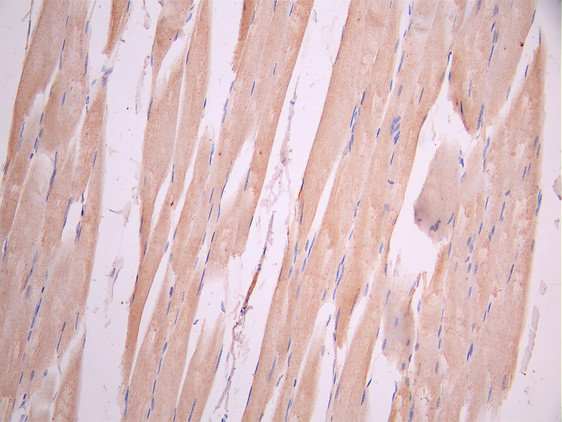

IHC image of CSB-RA061500A0HU diluted at 1:100 and staining in paraffin-embedded human skeletal muscle tissue performed on a Leica BondTM system. After dewaxing and hydration, antigen retrieval was mediated by high pressure in a citrate buffer (pH 6.0). Section was blocked with 10% normal goat serum 30min at RT. Then primary antibody (1% BSA) was incubated at 4°C overnight. The primary is detected by a Goat anti-rabbit polymer IgG labeled by HRP and visualized using 0.05% DAB.

Immunohistochemistry of paraffin-embedded human skeletal muscle tissue using CSB-PA812889LA01HU at dilution of 1:100